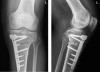

Figure 1.

The OW-HTO, Tomofix implant and tantalum beads used for RSA.